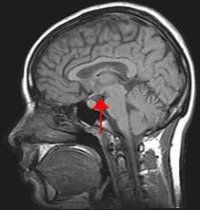

Situación do hipotálamo no cerebro

Científicos canadenses descubriron un mecanismo que podería axudar no tratamento dalgunhas enfermidades relacionadas coa memoria, segundo queda recollido na revista Annals of Neurology. A descuberta ocorreu accidentalmente, cando os expertos estaban a realizar unha exploración cirúrxica no cerebro dun home de 50 anos para intentar reducirlle o apetito e neutralizar a súa crecente obesidade.